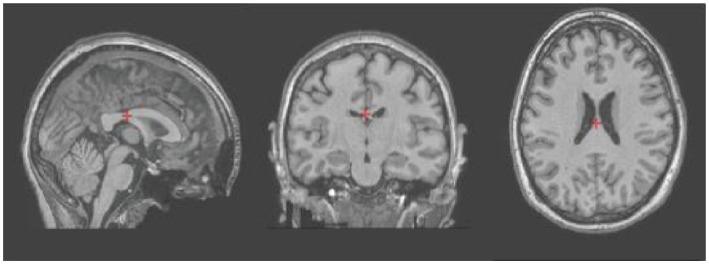

本研究证明了将云计算平台与基于课程的本科生研究体验(CUREs)相结合,以扩大神经科学教育的可及性的有效性。在连续四个春季学期(2021-2024)中,劳伦斯理工大学共有42名本科生参加了使用大脑生命的计算神经科学CUREs。云计算平台Io。学生们对公开可用的数据集进行解剖和功能脑成像分析,测试关于大脑结构变化的原始假设。该项目从最初的数据处理发展到假设驱动的研究,探索年龄、性别和病理对大脑结构的影响。通过在用户友好的云环境中结合开放科学和大数据,CURE模型为先前知识有限的学生提供了动手的、基于问题的学习。这种方法解决了传统本科生研究经历的主要局限性,包括可扩展性、早期曝光和包容性。学生们一直使用MRI数据集,专注于大脑结构的体积分析,并通过在年度研究日上展示研究结果来培养科学交流技能。这个项目的成功证明了它的潜力,使神经科学教育民主化,使先进的研究没有广泛的实验室设施或先前的经验,并促进原始的本科生研究使用现实世界的数据集。

This study demonstrates the effectiveness of integrating cloud computing platforms with Course-based Undergraduate Research Experiences (CUREs) to broaden access to neuroscience education. Over four consecutive spring semesters (2021-2024), a total of 42 undergraduate students at Lawrence Technological University participated in computational neuroscience CUREs using brainlife.io, a cloud-computing platform. Students conducted anatomical and functional brain imaging analyses on openly available datasets, testing original hypotheses about brain structure variations. The program evolved from initial data processing to hypothesis-driven research exploring the influence of age, gender, and pathology on brain structures. By combining open science and big data within a user-friendly cloud environment, the CURE model provided hands-on, problem-based learning to students with limited prior knowledge. This approach addressed key limitations of traditional undergraduate research experiences, including scalability, early exposure, and inclusivity. Students consistently worked with MRI datasets, focusing on volumetric analysis of brain structures, and developed scientific communication skills by presenting findings at annual research days. The success of this program demonstrates its potential to democratize neuroscience education, enabling advanced research without extensive laboratory facilities or prior experience, and promoting original undergraduate research using real-world datasets.